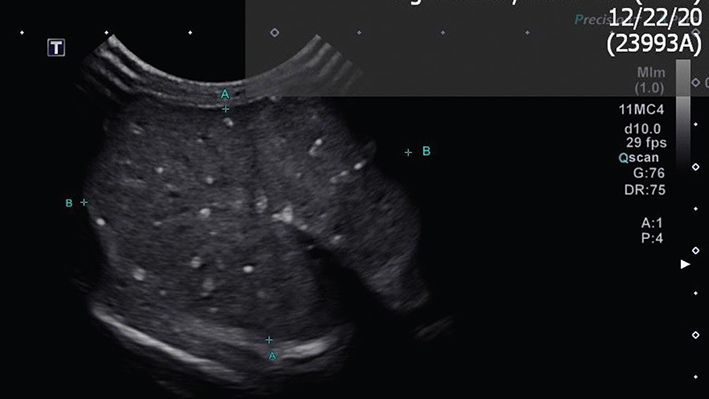

Case 2: A 3½ year, intact male Rottweiler with a history of prostate disease was presented for ultrasonographic evaluation in February of 2022. Testes were judged to be somewhat small and bilateral testicular microlithiasis was identified (Figures 5 and 6). Breeding soundness examination was performed in January of 2023. Abnormalities noted on general physical examination were mild dental disease and a grade III/VI cardiac murmur. Both testes were small, with an estimate of them being half the size expected for a dog of this breed and size. Semen was collected by manual ejaculation with no teaser female dog present but with exposure to estrous dog vaginal swabs. Libido was high; 4.5 ml of semen was collected and that was azoospermic. Semen alkaline phosphatase concentrations suggested incomplete ejaculation despite good libido and normal erection and reproductive behavior. Dog was castrated and testes were submitted for histopathology in April 2023. Both testes contained widely scattered foci (Figures 7 and 8; blue arrows) of intratubular mineralization (500 µm in maximal diameter with < 200 µm in diameter) without associated inflammation. Outside of these mineralized areas, there were rare small interstitial infiltrates of lymphocytes and plasma cells and rare individual atrophied seminiferous tubules.

Figure 7.

Figure 7. Testicular histopathology (low magnification) of Case 2

Figure 8.

Figure 8. Testicular histopathology (high magnification) of Case 2